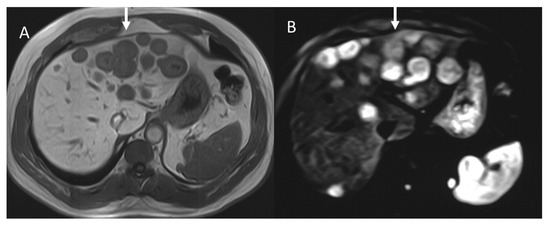

In the presence of unclear imaging results in the diagnosis of PNEN, CT radiomics can be helpful in determining the type of tumor. In fact, PNECs in the portal venous phase on CT with contrast media tend to show greater uniformity and less entropy than PDACs in the absence of significant differences in these parameters in the arterial phase, kurtosis, and asymmetry (heterogeneity parameters) [63]. The cut-off value of 0.34 has been suggested for uniformity in differentiating NEC from PDAC with a sensitivity and specificity of 79% and 65%, and a cut-off value of 1.89 for entropy with a sensitivity of 74% and a specificity of 70% [63]. Radiomics is also particularly useful in differentiating atypical PNENs that show hypovascularization in the CT arterial phase from PDACs [64]. In fact, the latter have a greater skewness (which is a measure of heterogeneity) than atypical PNETs with lower mean, median, fifth, tenth, and twenty-fifth percentiles on the entire tumor structure by contrast-enhanced CT (CECT) compared to those of atypical PNET. The authors suggest that this result could be linked to a greater cystic necrosis and degeneration. The fifth percentile alone or combined with asymmetry was capable in differentiating the two groups with high sensitivity: when considered alone, a sensitivity of 96% and a moderate specificity of 64% were reached, while in combination, a sensitivity of 90% and a specificity of 80% were reached [64]. In another study, it emerged that a model of seven radiomic characteristics can differentiate between atypical PDAC and PNET with greater sensitivity and specificity than the model based on clinical radiological parameters alone [65]. Neuroendocrine tumors can be differentiated from adenocarcinomas by histogram analysis performed in DWI of apparent diffusion coefficient (ADC) values on MRI (Figure 4). PDACs showed greater kurtosis (heterogeneity marker) and skewness in ADC histogram analysis on ADC400 (b value 0–400 s/mm2) and ADC800 (b value 0–800 s/mm2) than PNET tumors, while neuroendocrine tumors, as seen in the analysis of the CT texture, have a significantly lower entropy, regardless of the b value [66].

Figure 4.

MRI assessment of pancreatic NEN. In T2-W (A) sequence, the lesion (arrow) is inhomogeneous and hypo–hyperintense due to fibrotic component. This feature is evident in late phase (B) of contrast study (arrow). In DWI ((C): b800 s/mm2), the lesion (arrow) shows restricted diffusion with hypointense signal in ADC map (arrow in (D)).